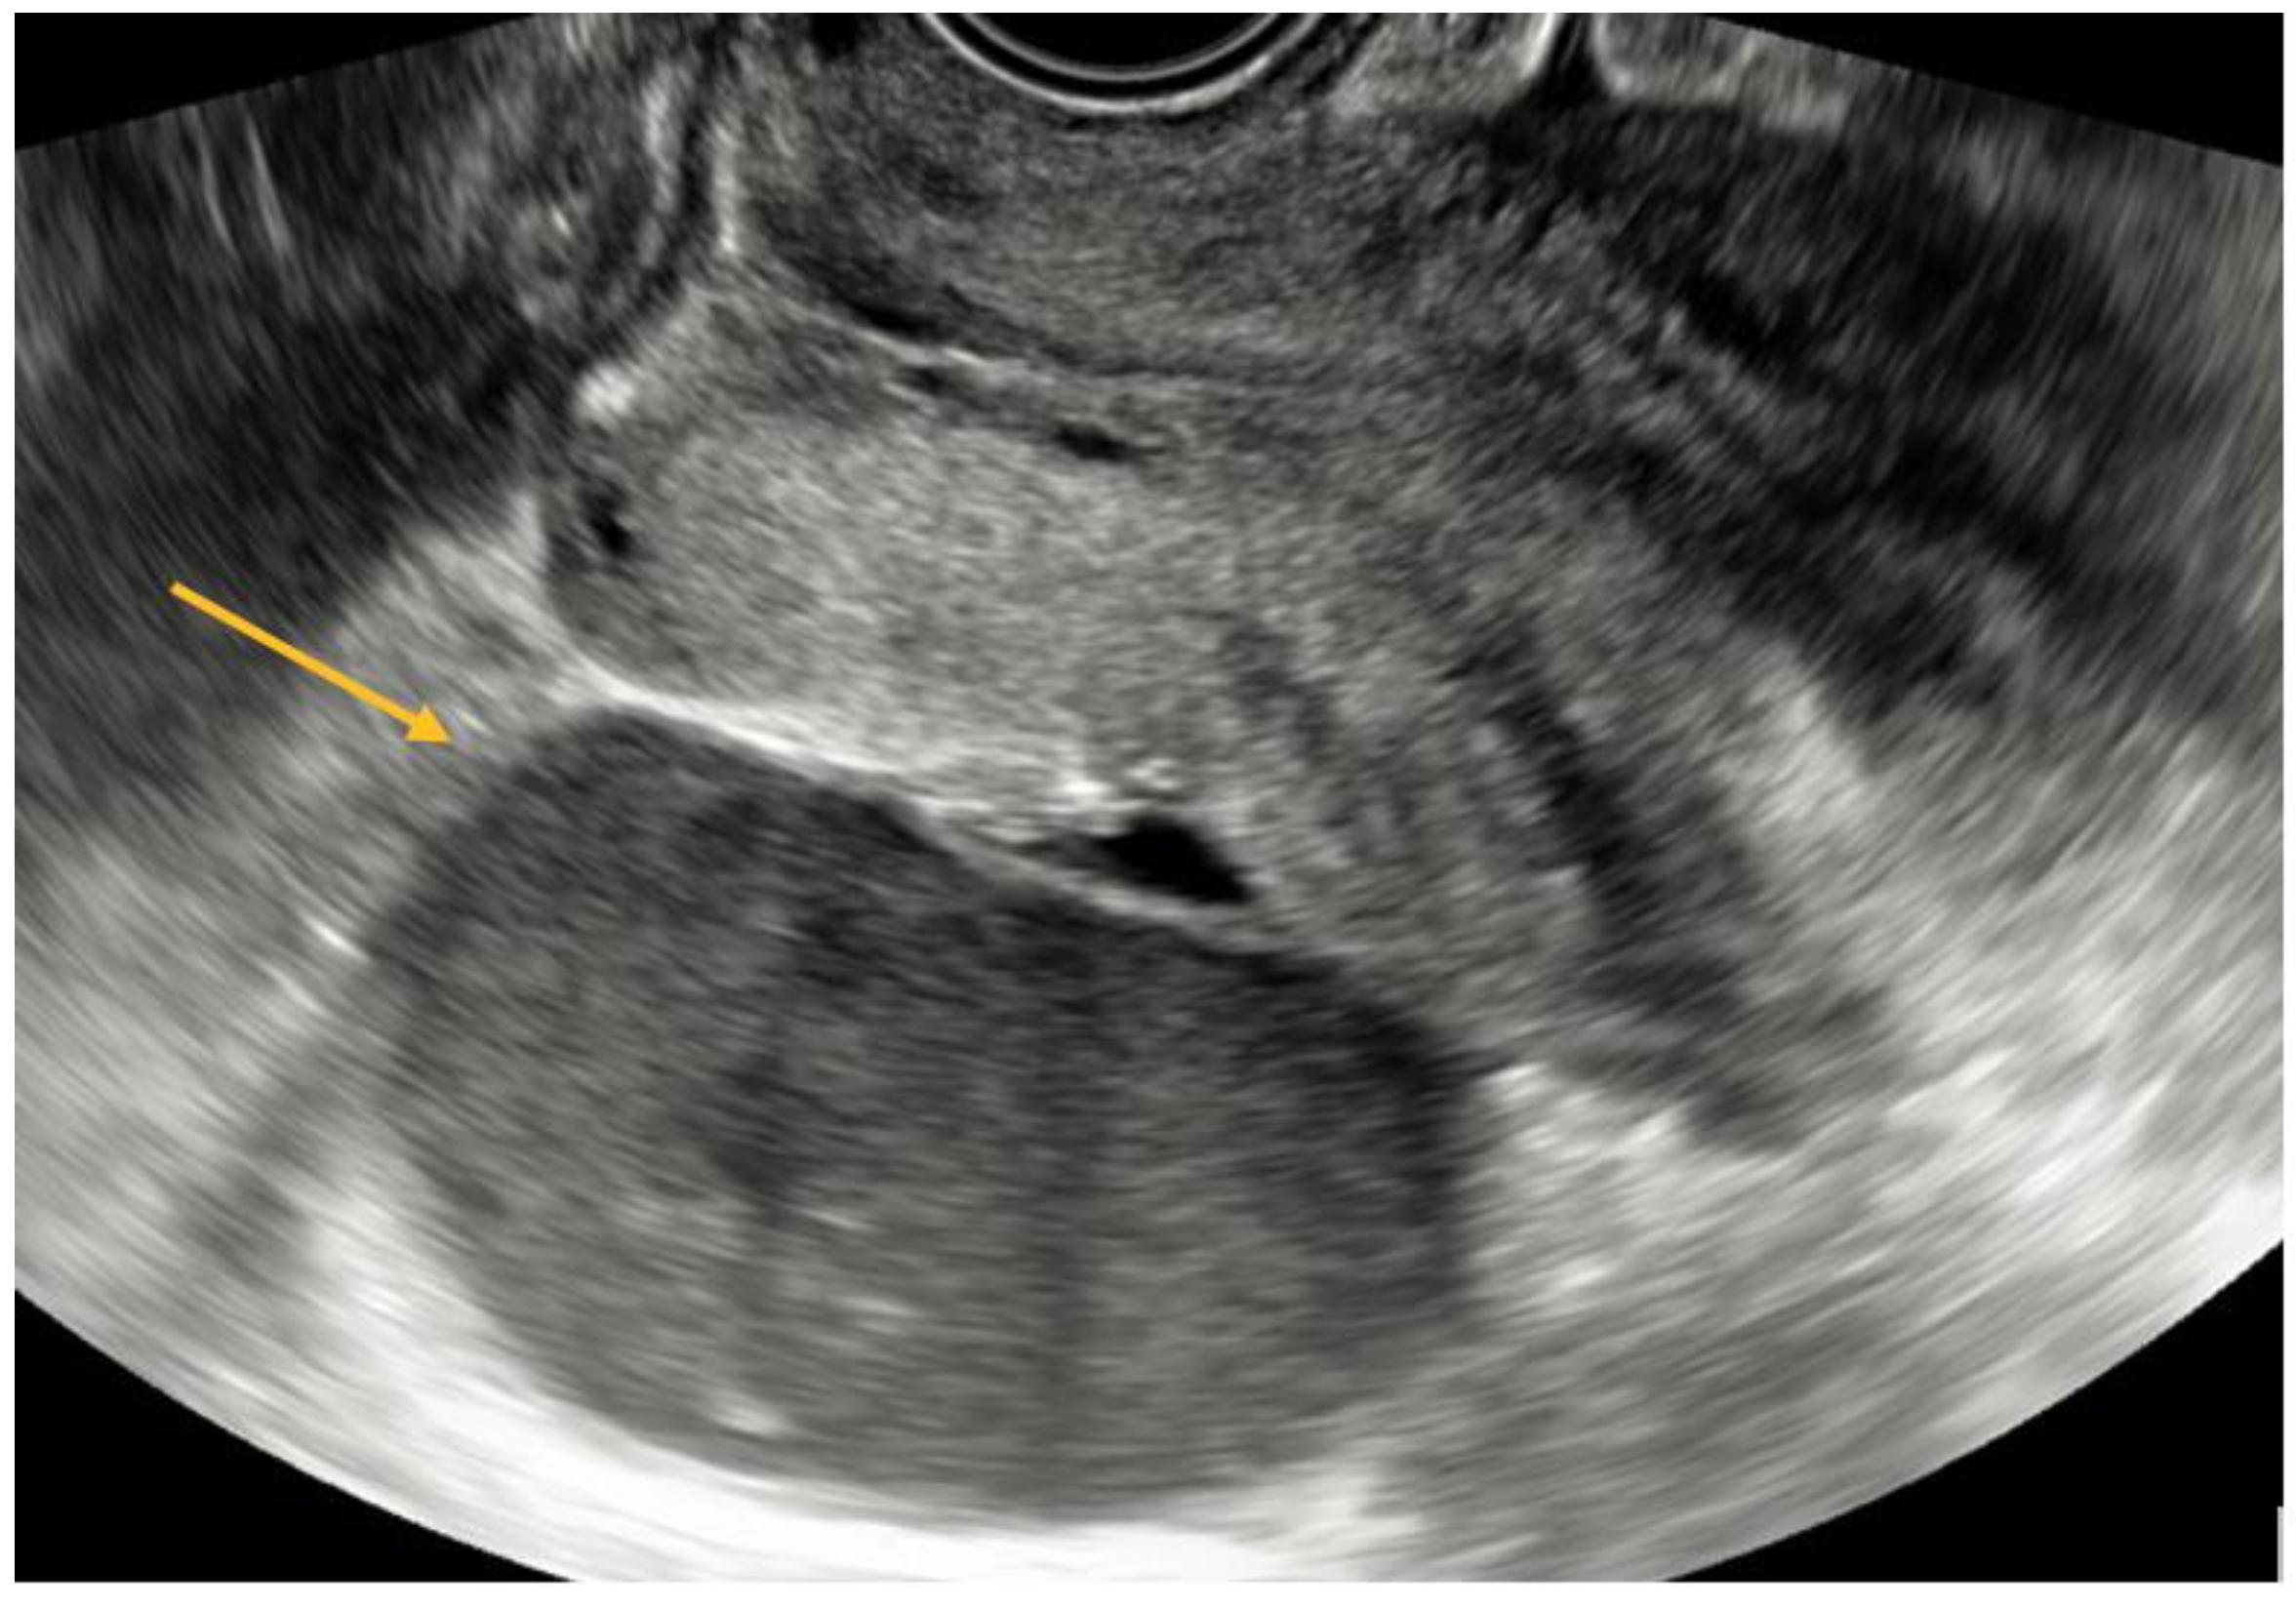

TVS is a reliable diagnostic tool for ovarian endometriomas (OMA), which can be readily identified due to their characteristic ground-glass appearance, which lacks any discernible vascular echo when assessed with a Doppler flow scanner, as depicted in Figure 3 [9,10].

The statistical analyses, namely the Chi-square χ2 test (df = 1) = 80.85, p < 0.001, and Fisher’s exact test p < 0.001, indicate a statistically significant connection. Therefore, within this cohort, the ultrasound diagnostic aligns with the intraoperative diagnosis for endometriomas. The specificity of the diagnostic test is 57.14%, indicating that it correctly identifies individuals without the condition. The sensitivity is 93.78%, indicating that it accurately detects individuals with the condition. The diagnostic accuracy, which is a significant measure, is 84.47%. The value of Cohen’s kappa coefficient was found to be 0.55, which indicates a moderate level of agreement. The statistical significance of this result was confirmed with a p-value < 0.001.

Figure 3. TVS aspect of endometrioma.